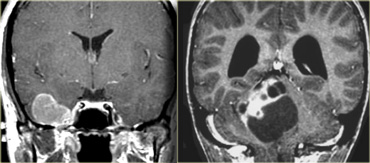

Schwannoma in CPA-region with typical features of an extraaxial tumor (T2WI) Schwannoma in CPA-region with typical features of an extraaxial tumor (T2WI)

The T2W-images show a schwannoma located in the cerebellopontine angle (CPA).

This case nicely demonstrates the typical signs of an extra-axial tumor.

There is a CSF cleft (yellow arrow).

The subarachnoid vessels that run on the surface of the brain are displaced by the lesion (blue arrow).

There is gray matter between the lesion and the white matter (curved red arrow).

The subarachnoid space is widened because growth of an extra-axial lesion tends to push away the brain.

All these signs indicate that this is a typical extra-axial tumor.

In the region of the CPA 90% of the extra-axial tumors are schwannomas.